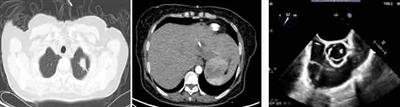

通过转诊绿色通道,患者被第一时间转入本部呼吸与危重医学一科。入院后复查影像:胸部左肺团块、斑片灶,考虑肺脓肿;肝左叶团状蜂窝,考虑肝脓肿;心脏超声示主动脉瓣赘生物。

魏东主任医师立即带领赵伟业副主任医师、吕森森副主任医师进行病情分析:患者因长期未能有效控血糖,导致身体免疫力低下,营养丰富的血液成了细菌培养基,起初一点点的感染逐步加重至严重感染,肝脏内形成接近一个拳头大小的脓腔,肺部病灶均位于胸膜下考虑血源性感染,疑惑的是左上肺病灶呈现“鬼脸征”,同时还伴有感染性心内膜炎及瓣膜赘生物形成。科室立即组织肝胆外科、心外科多学科会诊,专家讨论认为,脓肿治疗的关键在于引流,外院应用广谱抗生素治疗效果不好的原因在于未引流脓肿。为了更快揪出致病菌,急请B超室在超声定位下进行了经皮肝脓肿穿刺引流,不断有砖红色的脓液排出患者体外。穿刺液中白细胞高达182279.00×10^6。

在焦急的等待中,微生物室汇报:肝脏穿刺液细菌培养结果为肺炎克雷伯菌,拉丝试验阳性。集团副院长、本部呼吸与危重医学科主任刘学东主任医师查房指出:患者免疫力受损,肺炎克雷伯菌感染明确,拉丝试验阳性代表菌株为高黏表型并具有高毒力。

肺炎克雷伯菌可以自然存在于健康个体的肠道和呼吸道中,具有健康免疫系统的人很少发生感染疾病。高毒力肺炎克雷伯菌感染以肝脓肿最为常见,并可转移到肺、脑和眼等部位,称之为侵袭性肝脓肿综合征,病情凶险,死亡率高。不仅如此,患者入院还出现了感染性心内膜炎及瓣膜赘生物的征象,hvKP感染导致心内膜炎罕见。